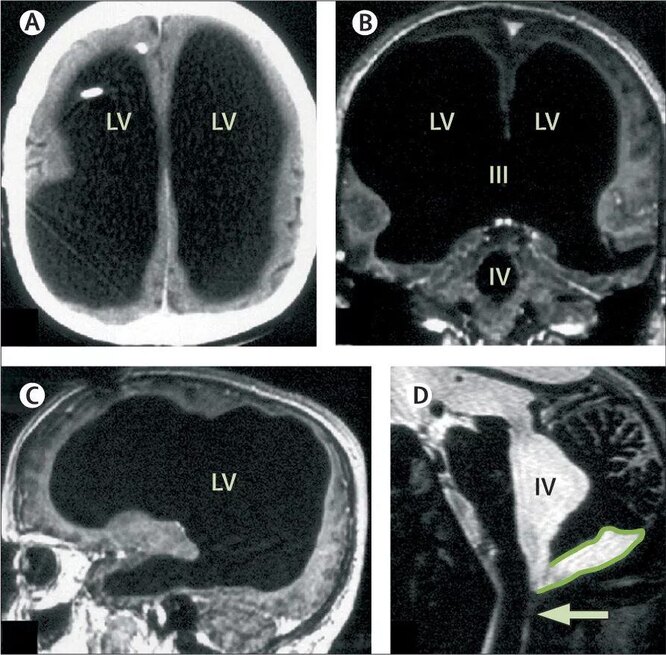

Некоторые люди практически и без мозга (аварии, болезни...) нормально себе живут.

Сознание может существовать независимо от мозга.